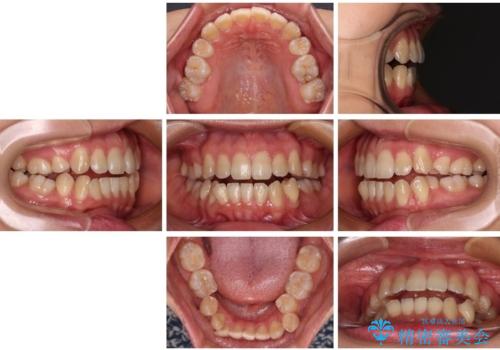

非接触の前歯と下顎のデコボコ ワイヤー装置による矯正治療

- 上下顎前歯部の非接触(開咬)と下顎のデコボコを主訴に来院された患者様です。

右側上下と左上の小臼歯が一本ずつ少なく、さらに骨格的な左右差もあり上下の真ん中の位置がずれています。

下顎のデコボコの解消と、真ん中の位置を改善するために左下の小臼歯を抜歯することとしました。

また、開咬を改善するため臼歯部にアンカースクリューを用いて圧下する力をかけていきました。

舌を突出する癖があり、それにより開咬が悪化したり、後戻りの原因になるため、舌のトレーニング(MFT)も行いました。

舌のトレーニングは継続して行ってもらっているため、開咬や抜歯したスペースの後戻りはなく、経過は良好です。